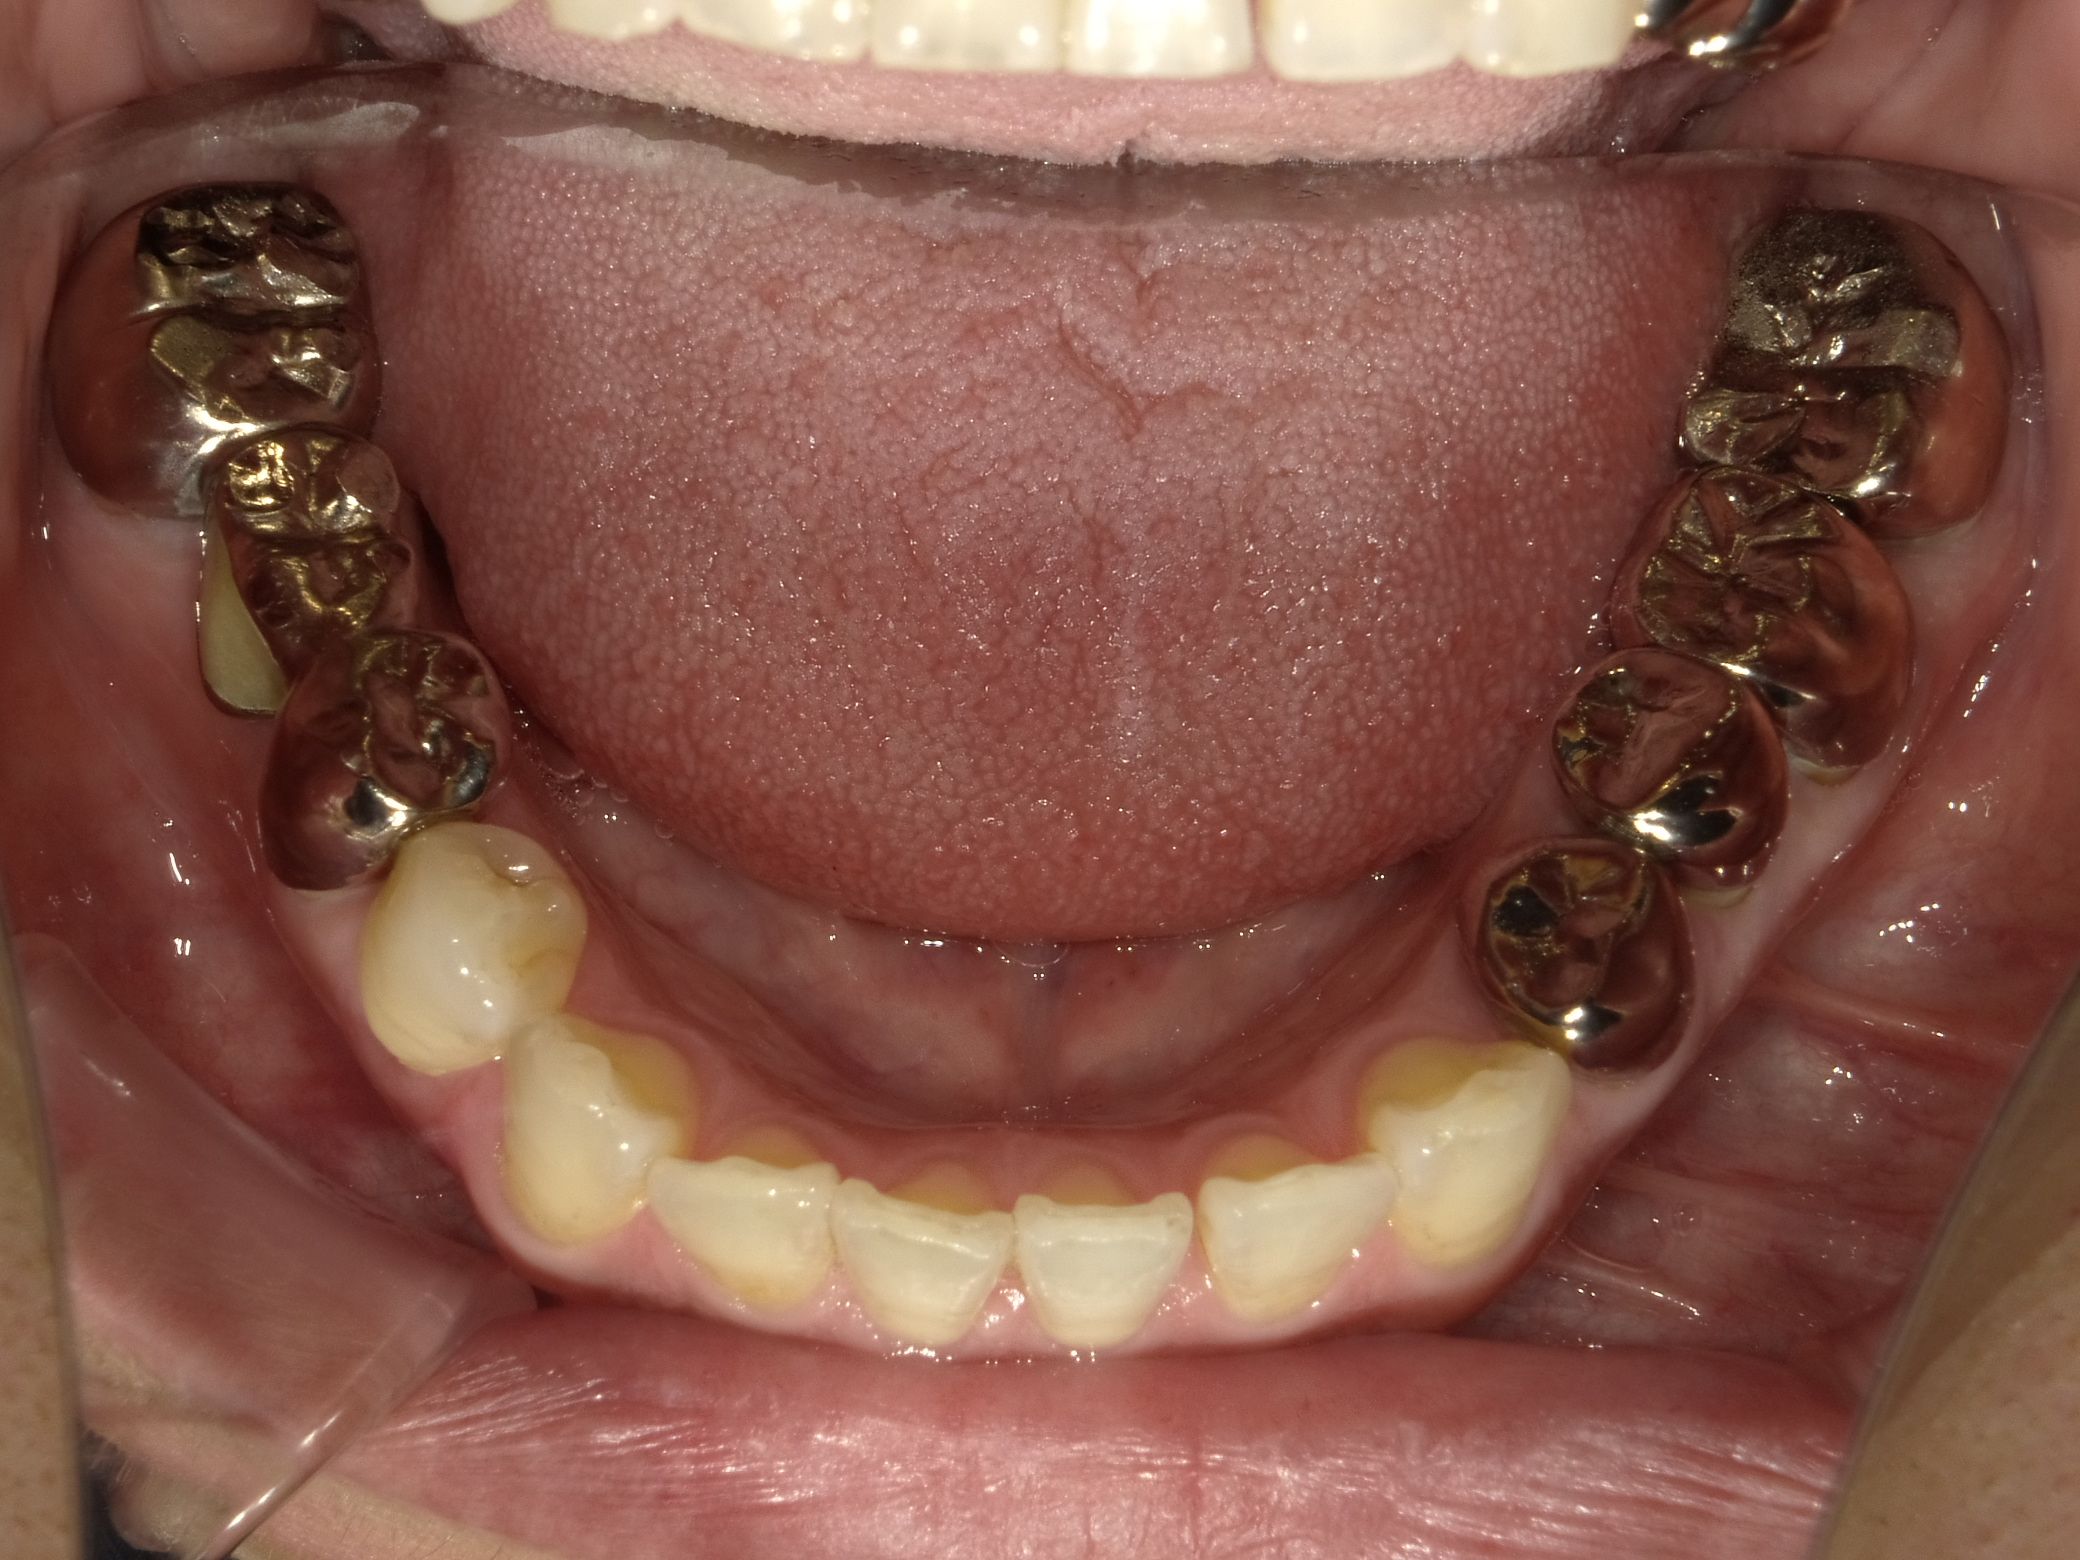

銀歯(金銀パラジウム合金)

ニッケル・パラジウム・銀・金・銅、亜鉛などが混ざった合金。

適合性:セメントが劣化し、徐々に隙間があいてくる

二次むし歯:セメント劣化の隙間から汚れや菌が入り込み、虫歯リスク高まる

安全性:アレルギーの基となる成分が体に蓄積し、金属アレルギーの原因になる

耐久性:十分あるため、奥歯の治療に適している

審美性:存在感あり。